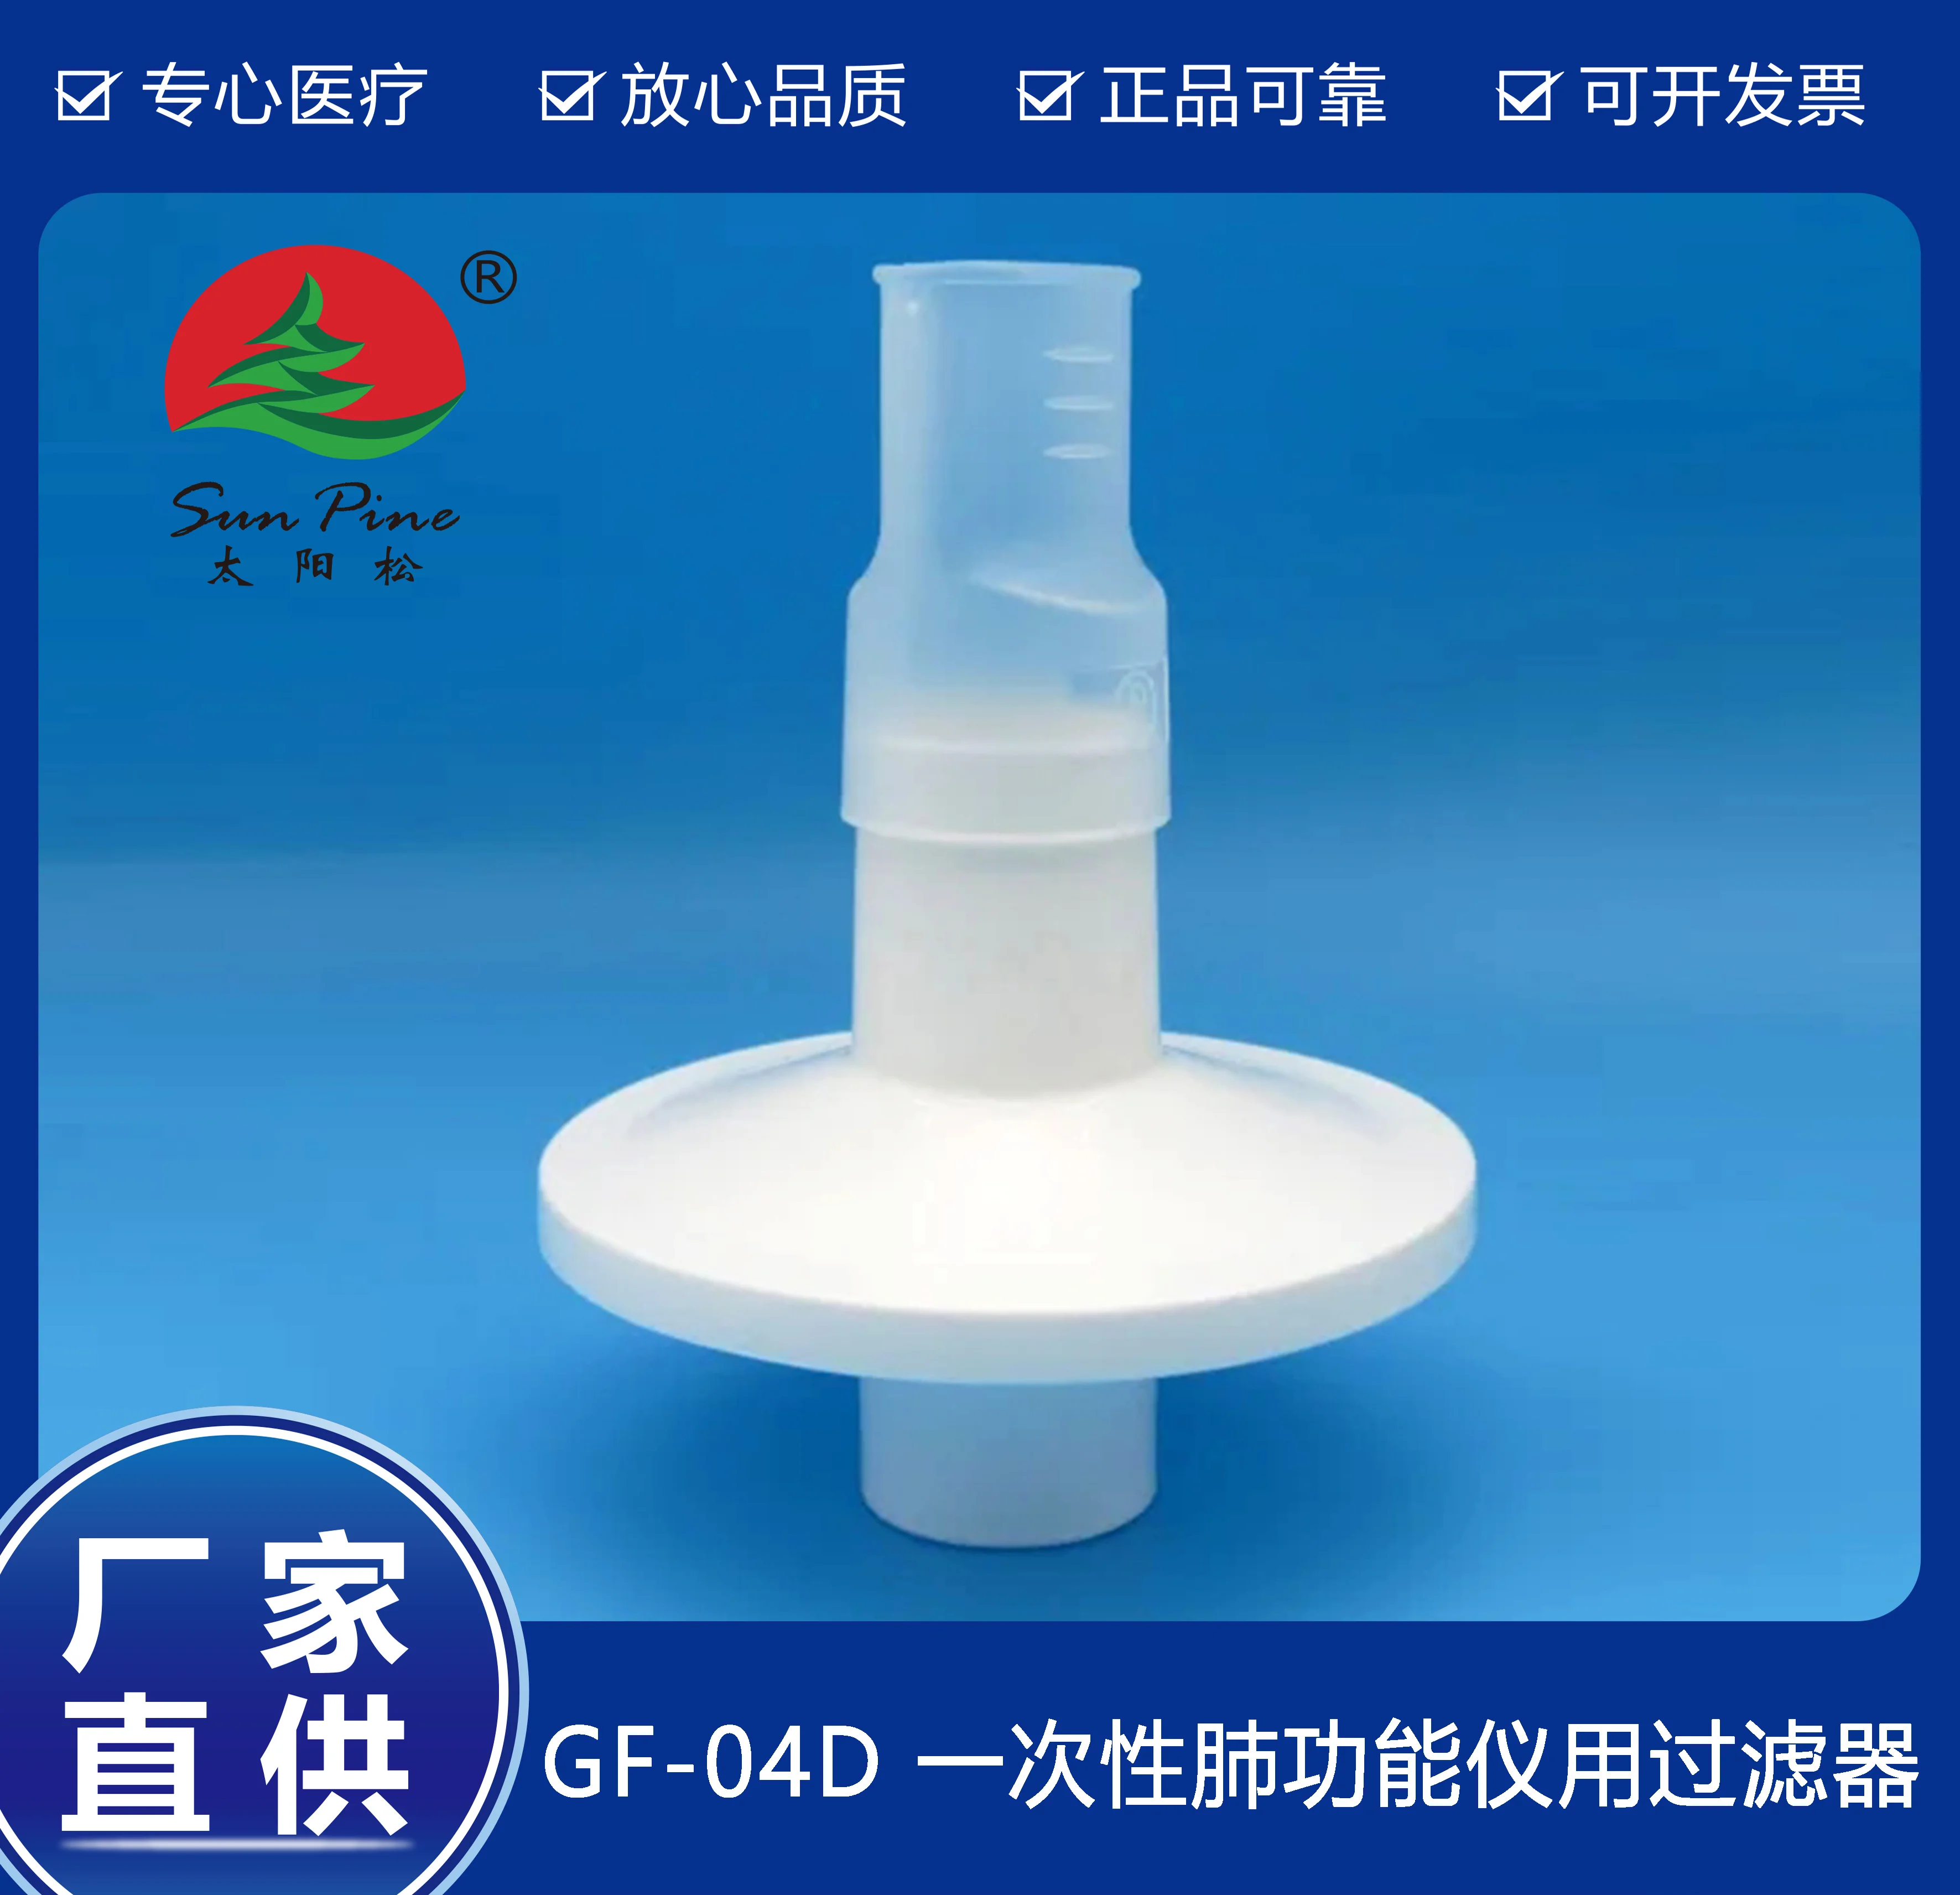

中山高榮電子科技有限公司是一家集自主研制,生產(chǎn)和銷(xiāo)售一體的高新技術(shù)醫(yī)療器械生產(chǎn)企業(yè),嚴(yán)格按照CFDA認(rèn)證,遵守國(guó)家醫(yī)療器械法規(guī)建立了完善的質(zhì)量管理體系,確保提供給客戶(hù)的醫(yī)療器械產(chǎn)品安全健康。公司擁有十萬(wàn)級(jí)、萬(wàn)級(jí)潔凈生產(chǎn)車(chē)間,環(huán)氧乙烷滅菌車(chē)間,有專(zhuān)門(mén)的物理實(shí)驗(yàn)室、理化實(shí)驗(yàn)室和微生物實(shí)驗(yàn)室以及醫(yī)電研發(fā)室、醫(yī)電生產(chǎn)車(chē)間。主要產(chǎn)品有:“太陽(yáng)松”品牌:一次性使用呼吸過(guò)濾器,一次性肺功能儀用過(guò)濾器,咬嘴;“凱華”品牌:醫(yī)用電子產(chǎn)品,肺功能檢查儀等,其中過(guò)濾器,咬嘴可匹配市場(chǎng)上各種不同品牌型號(hào)的肺功能儀使用,可以降低患者吸入或呼出顆粒性物質(zhì)的數(shù)量,防止污染儀器,大限度保障每位受測(cè)者健康安全.